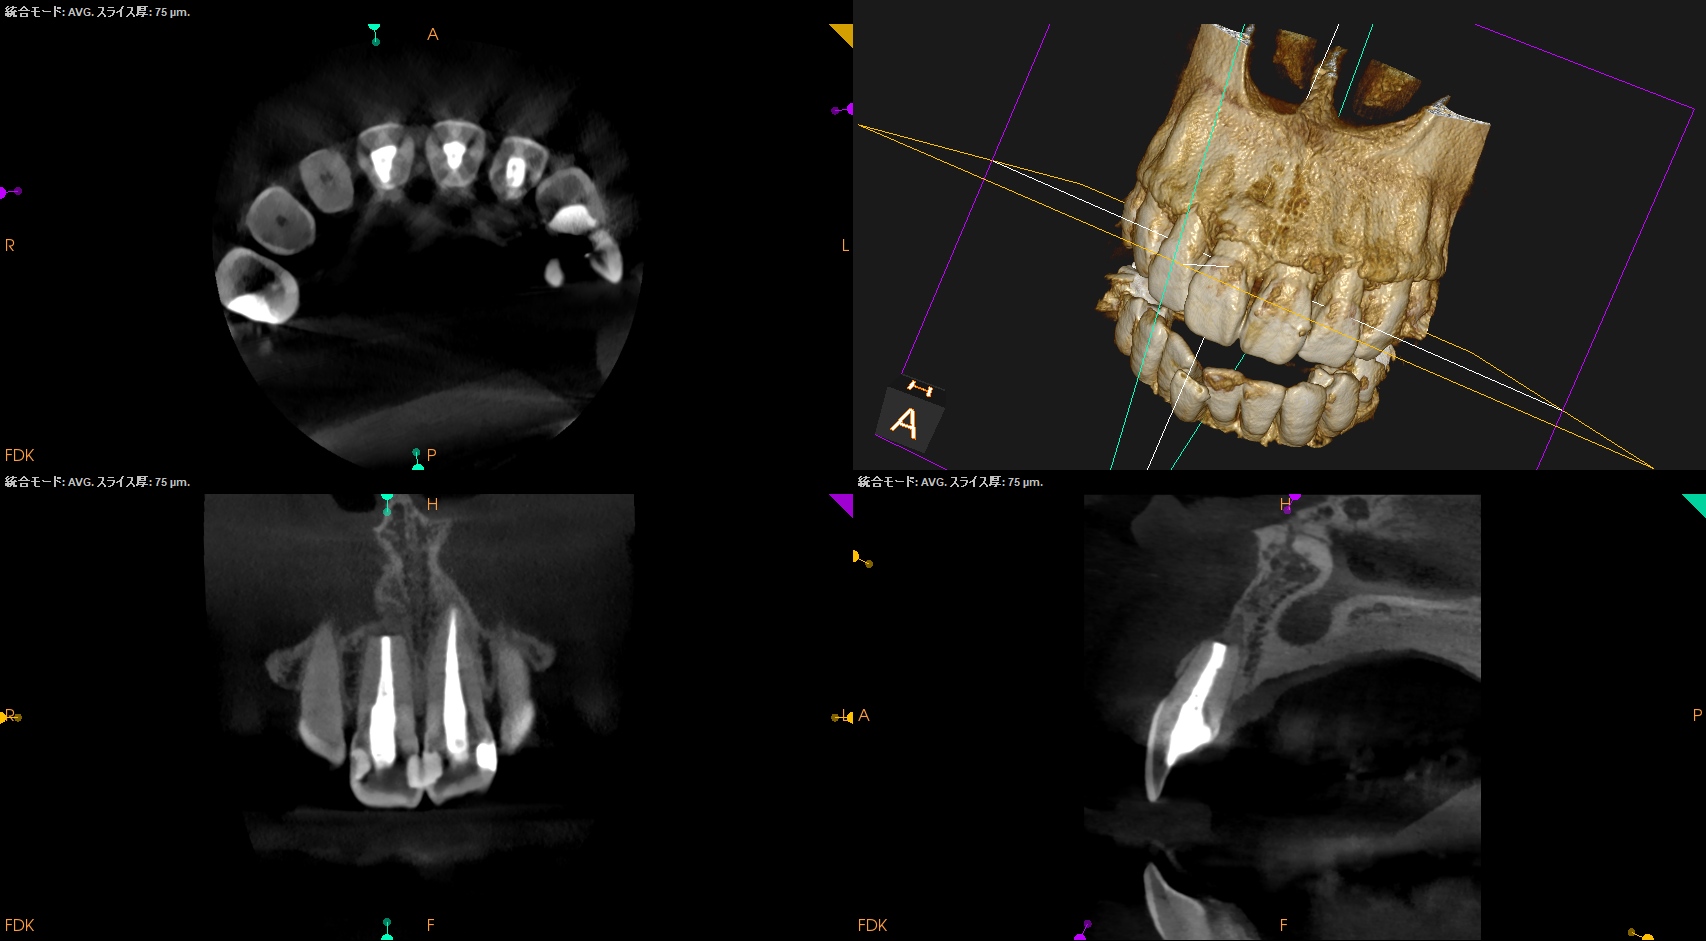

CBCT(2025.6.3)

#8はApexが歯槽骨からはみ出ている。

PA所見から考察するに、再治療よりも外科治療だろう。

#8 Apicoectomy 6M recall(2025.12.2)

PA, CBCTを撮影した。

初診時と比較した。

劇的に状況は改善している。